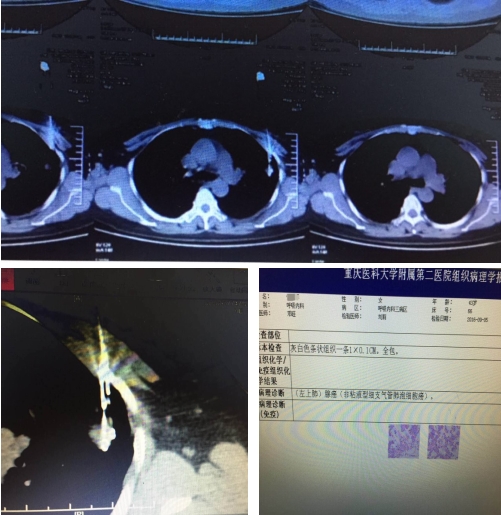

呼吸内科副主任李长毅副教授,成功为一左上肺0.8-1CM小结节患者实施CT引导下经皮肺穿。此次操作,是我院首次成功穿刺不足1CM微小病灶,标志着我科的肺穿技术达到国内领先水平。

该女性患者发作性喘息多年,院外CT结果显示:左上肺0.8-1CM小结节。提示:不排除肺癌可能。肺癌在恶性肿瘤的死因中占首位,早期及时的诊断及治疗,对患者的预后效果、生存时间及质量,具有重大意义。CT引导下经皮肺穿刺活检,可以准确显示病灶本身情况及与周围组织结构的解剖关系。其病理诊断对治疗具有至关重要的作用。

结节病灶越小,离胸壁越远,定位越困难,越考验穿刺者的专业水准。该患者的病灶过于微小,目前国内也很少有能成功穿刺不足1CM病灶的病例。此次操作,需要操作者精准确定进针部位、角度及深度,稍有不慎,便易造成气胸、肺出血等并发症。经过胸部扫描,选取左侧胸壁穿刺点,并明确穿刺深度,李长毅副教授凭借10多年的临床经验,精湛的穿刺技术及耐心的操作,终于完成了这例操作难度较大,复杂程度高的穿刺手术。后组织病理学检查报告:左上肺腺癌(非粘液型细支气管肺泡细胞腺癌)。

此次微小病灶的精准穿刺技术极大丰富了我科对CT引导下经皮肺穿的经验,也为肺部疾病患者实现高难度肺穿手术提供了保障,对于肺内病灶的临床定性诊断、制定治疗方案及预后有极大的帮助。